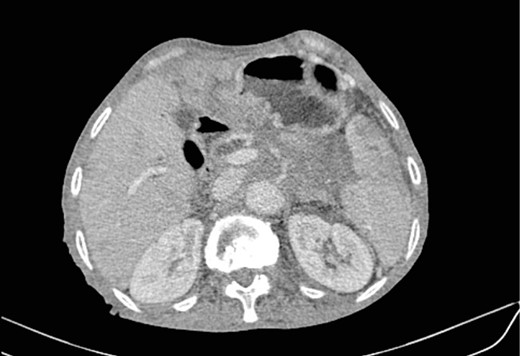

Mr. A. is a 65-year-old hypertensive patient presenting with acute epigastric pain associated with abdominal bloating. Biological settings showed amylasemia at 450 IU/L and lipasemia at 525 IU/L. Abdominal CT scan revealed heterogenous poorly defined mass in the pancreatic head with low enhancement (Figs 1 and 2). The CA 19–9 assay was 280 IU/L. Cephalic duodenopancreatectomy was performed. Histological examination of the operative specimen revealed a solid, trabecular, undifferentiated carcinomatous process (Fig. 3) expressing markers (CK(AE1-AE3) and p40) (Fig. 4), confirming the diagnosis of primary squamous cell carcinoma of the pancreas. The extension study showed no secondary localization.

Low-enhancing poorly defined mass in the pancreatic head with surrounding fat stranding (arrow).